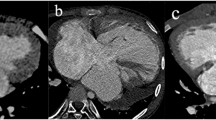

The coronary artery patterns of the study population evaluated with cardiac CT, transthoracic echocardiography, and a surgeon’s eyes are summarized in Table 2. The most common coronary artery pattern of the study population was the usual pattern (64.4%, 65/101), in which the left coronary artery arises from sinus 1 and the right coronary artery originates from sinus 2 (Fig. 1). The second most common finding was a single coronary artery from sinus 2 and a conal branch from sinus 1 (7.9%, 8/101; Figs. 2), followed by the inverted pattern in which the right coronary artery arises from sinus 1 and the left coronary artery originates from sinus 2 (5.9%, 6/101; Fig. 3) and the right coronary artery and left anterior descending artery from sinus 1 and the left circumflex artery from sinus 2 (5.9%, 6/101; Fig. 4). Of note, in a single coronary artery arising from sinus 2 with or without a conal branch from sinus 1 correctly identified on cardiac CT (n=12), cardiac CT could accurately distinguish between a double orifice (n=2; Fig. 5) and a single orifice (n=10; Fig. 6) as well as between an anterior coronary looping (n=2; Fig. 7) and a posterior coronary looping (n=10; Fig. 2).

Imaging in a 3-day-old girl born with transposition of the great arteries and ventricular septal defect. a–c Cardiac CT images show the usual coronary artery pattern in which the left coronary artery arises from sinus 1 and the right coronary artery originates from sinus 2. Axial oblique section (a) demonstrates both coronary artery origins. Coronal oblique section (b) best demonstrates the right coronary artery. Coronal oblique section (c) best demonstrates the left coronary artery. d, e Transthoracic echocardiographic images also demonstrate the usual patterns of the left (d) and right (e) coronary arteries that was subsequently confirmed at arterial switch operation. 1 sinus 1, 2 sinus 2, AA ascending aorta, DA descending aorta, LA left atrium, LAD left anterior descending artery, LCA left coronary artery, LCx left circumflex artery, PT pulmonary trunk, RA right atrium, RCA right coronary artery, RV right ventricle

Imaging in a 5-day-old boy born with transposition of the great arteries, ventricular septal defect and coarctation of the aorta. Axial oblique (a) and coronal oblique (b, c) cardiac CT images of the left (a) and right (b) coronary arteries, and of conal branches (c) show a single coronary artery from sinus 2 and a conal branch from sinus 1 that was proved to be correct at arterial switch operation. Of note, the left coronary artery runs posterior to the pulmonary trunk, constituting posterior looping (a). 1 sinus 1, 2 sinus 2, AA ascending aorta, C conal branch, LA left atrium, LAD left anterior descending artery, LCA left coronary artery, LCx left circumflex artery, LV left ventricle, PT pulmonary trunk, RA right atrium, RCA right coronary artery, RV right ventricle

Imaging in a 2-day-old boy born with transposition of the great arteries and ventricular septal defect and who underwent balloon atrial septostomy 1 day prior. a–c Cardiac CT images show the inverted coronary artery pattern in which the right coronary artery arises from sinus 1 and the left coronary artery originates from sinus 2. Axial oblique section (a) demonstrates both coronary artery origins. Coronal oblique section (b) best demonstrates the right coronary artery. Coronal oblique section (c) best demonstrates the left coronary artery. d Transthoracic echocardiographic image also demonstrates the inverted coronary artery pattern that was subsequently confirmed at arterial switch operation. Side-by-side relationship of the great arteries is noted on both cardiac CT and transthoracic echocardiography. 1 sinus 1, 2 sinus 2, AA ascending aorta, DA descending aorta, LA left atrium, LAD left anterior descending artery, LCA left coronary artery, LCx left circumflex artery, LV left ventricle, PT pulmonary trunk, RA right atrium, RCA right coronary artery, RV right ventricle